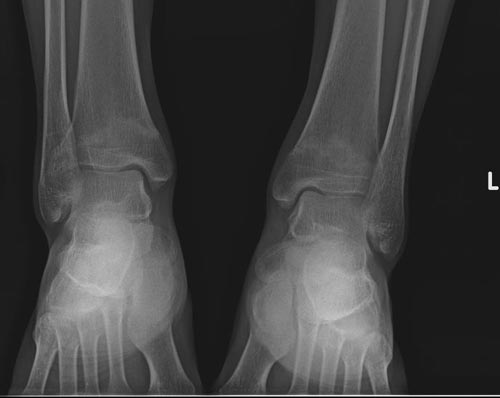

x线检查月前片示双踝关节骨质未见明显异常。一月后肿胀大部消失,疼痛稍有好转,摄片示两侧骨下段条带状高密度影,边界尚清。ct扫描示两侧胫骨下段骨皮质增厚不明显,髓腔内密度显示磨玻璃样增高,髓腔显示狭窄。

双胫骨下段近骨端处可见对称性增生硬化,骨小梁增粗但纹理尚清晰,未见明显骨质破坏,临近关节及关节囊未见明显异常。

双侧胫骨远端松质骨内见不规则密度增高影,且均以内侧为主,内侧骨皮质边缘欠清晰.临床提示月前稍运动后踝关节肿大。我考虑双侧胫骨低毒感染。

x线检查一个月前示双踝关节骨质未见异常。一个月后肿胀大部消失,疼痛稍有好转,摄片示两侧胫骨下段横行条状高密度影,边界较清。ct扫描示:两侧胫骨下段未见骨皮质增厚,两胫骨下段近骨端处可见骨小梁增粗但纹理尚清晰,未见明显骨质破坏,邻近关节及关节囊未见明显异常,软组织内未见异常.综上所诉考虑1.低毒感染所致,2.假性痛风

x线片表现为双侧胫骨下端粗条状磨玻璃样增高密度影,并可见骨皮质稍不连续。ct表现为双侧胫骨下端髓腔内磨玻璃样增高密度影,未见明显骨皮质不连续(可能与扫描体位有关)。

本例应该考虑为双侧胫骨下端应力性骨折。